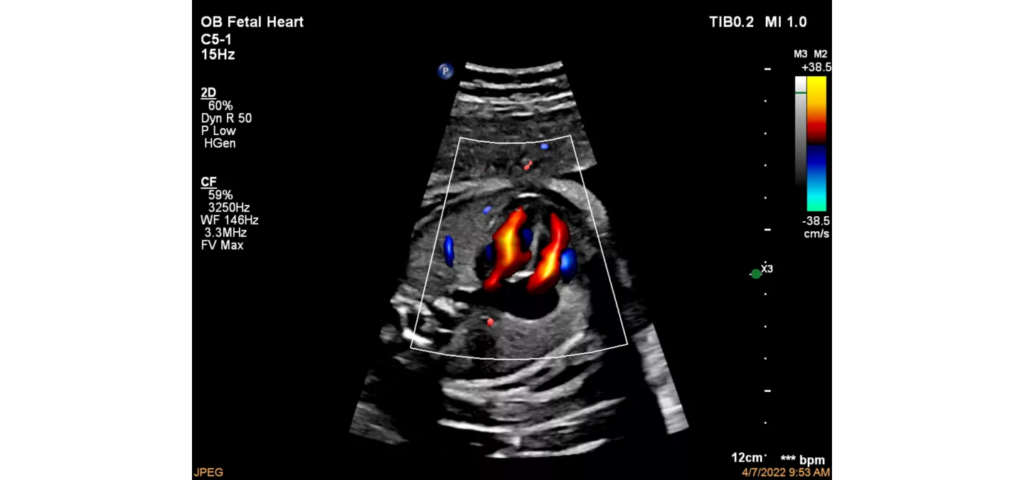

Philips EPIQ Elite ultrasound features an exceptional level of clinical performance, workflow, and advanced intelligence to meet the challenges of today’s most demanding practices. The EPIQ Elite platform brings ultimate solutions to ultrasound, with clinically tailored tools designed to elevate diagnostic confidence to new levels.